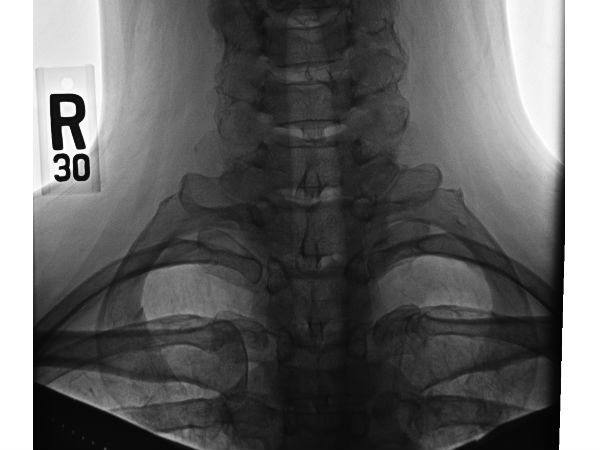

கழுத்து விலா எலும்பு!

இந்த எலும்பு 0.5% மக்களிடையே தான் இருக்கிறது என்றும், சிலருக்கு வலது புறமும், சிலருக்கு இடது புறமும் உடலில் காணப்படுகிறது என கூறுகிறார்கள். இதில் ஆச்சரியம் என்னெவென்றால் பறவைகளுக்கு இன்னும் இந்த எலும்பு இருக்கிறது. ஆனால், இந்த எலும்பு பகுதி மனிதர்கள் மத்தியில் வரும் காலத்தில் முற்றிலுமாக மறைந்து போகலாம் என கருதப்படுகிறது.